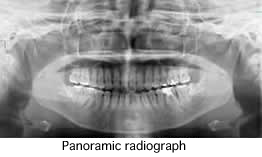

What is panoramic tomograph ?